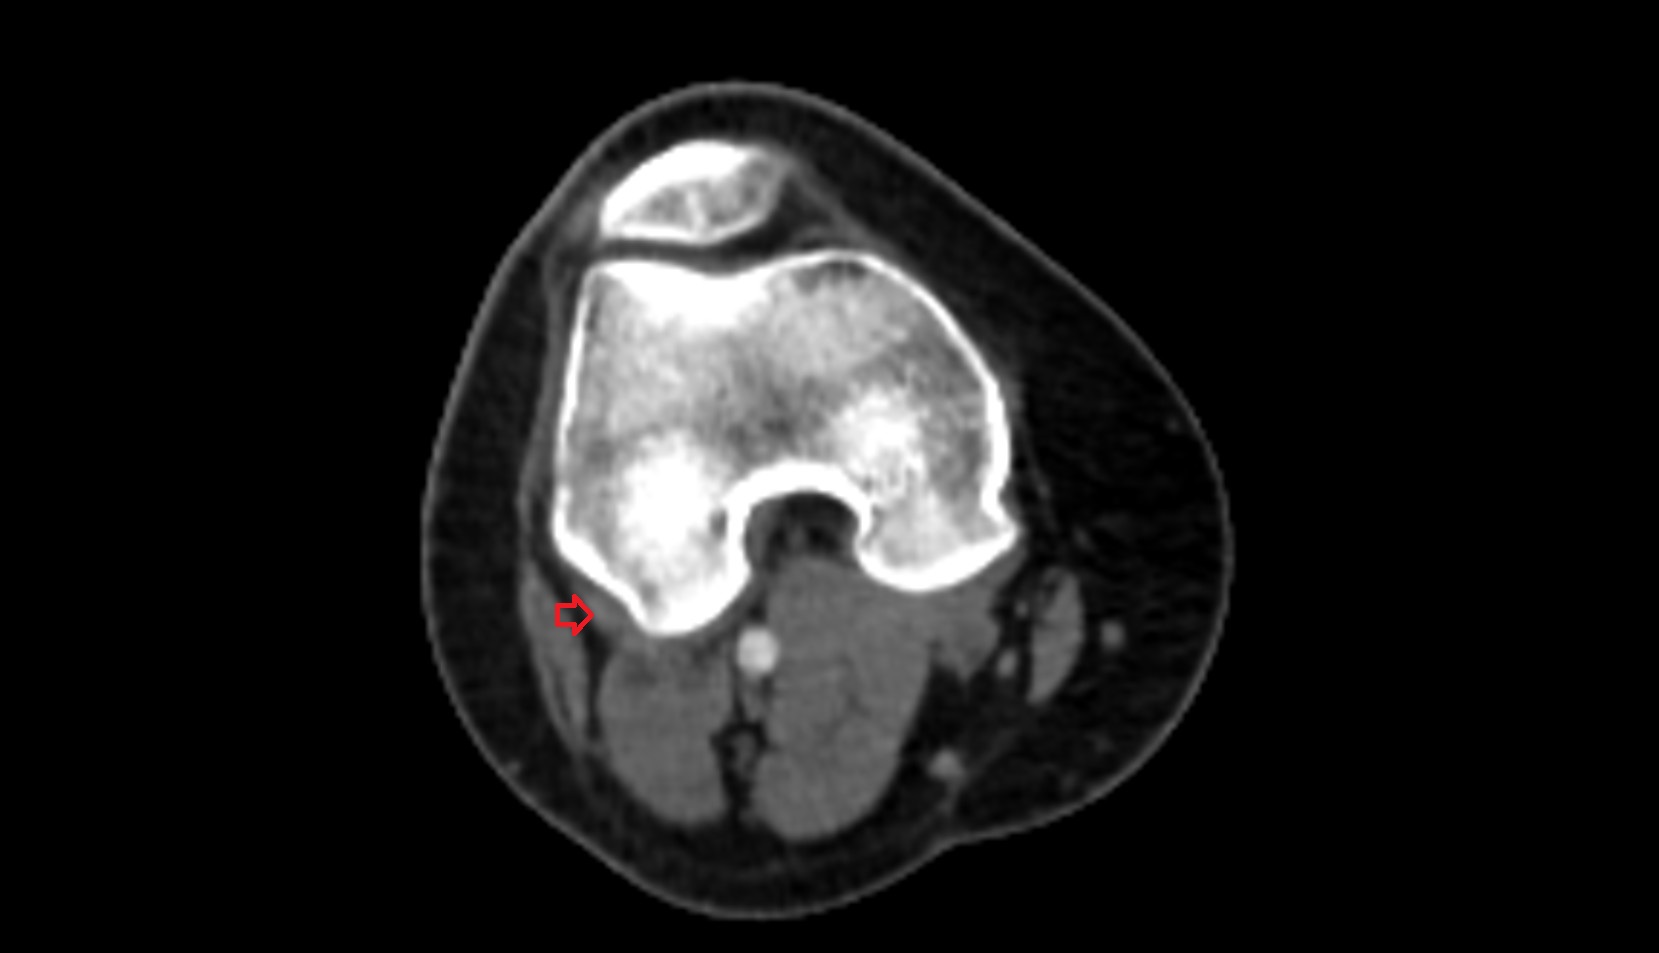

- Knee Joint